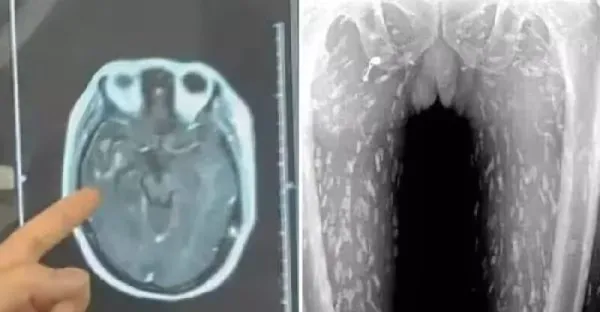

男子「吃魚」全身瘙癢以為過敏!一照X光「整片密密麻麻」嚇傻,醫警告:恐入侵大腦